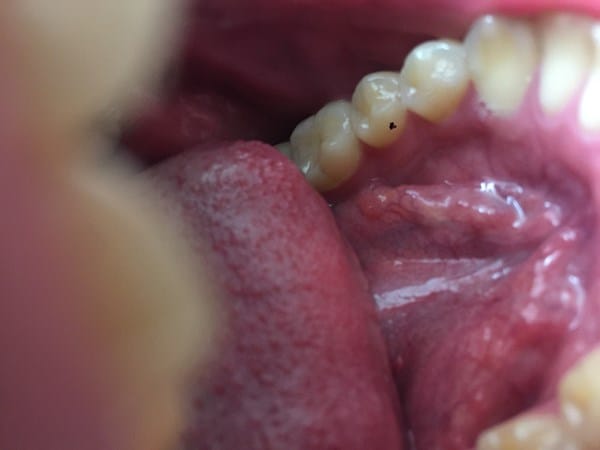

¿Siento cómo una ampolla debajo en la base de la boca debajo de la lengua? Que puede ser

Estuve leyendo y parece un mucocele no lo se, no me molesta ni nada no duele, solo cuando muevo mucho la lengua tocándomelo aveces si como que molesta. Pero en general si no me paso la lengua por ahí es como si no existiera, resulta que me traumó mucho con las cosas que aveces tengo.

al lado de la brusca que tiene la camara se ve como una ampolla.